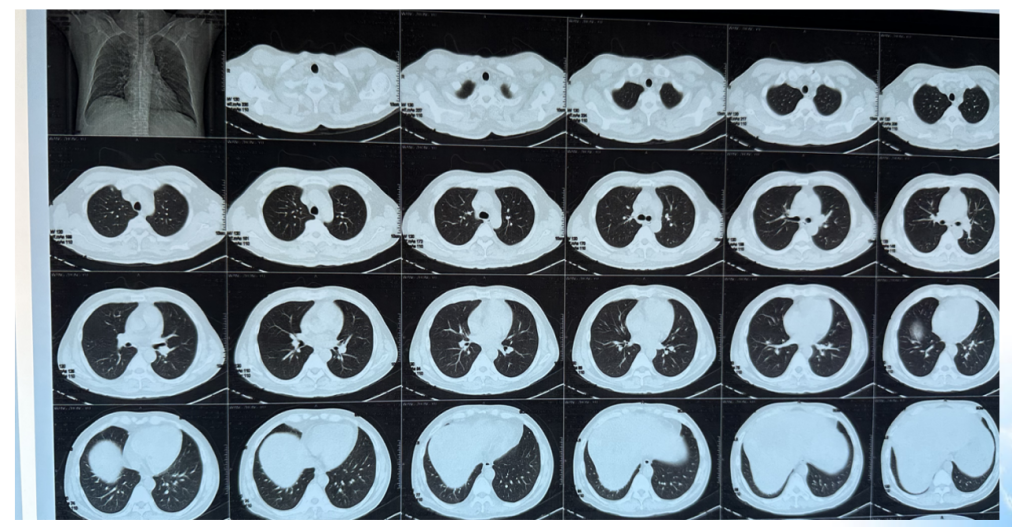

影像学检查:2024年7月30日,院外腹部CT显示乙状结肠管壁增厚,考虑肿瘤性病变(cT3N2,图1),2024年8月5日,肝脏MRI显示肝脏多发转移灶(侵犯门静脉右支、肝右静脉,图2)。2024年8月2日胸部CT显示双肺结节待排(图3)。

目前诊断:乙状结肠腺癌伴肝转移(cT3N2M1a IVA期) NRAS p.Q61L突变,TMB 6.2,MSS;中度贫血;双肺多发结节,转移待排(图7)。

目前诊断:乙状结肠腺癌伴肝转移;肝动脉内钇90放射治疗后;中度贫血;双肺多发结节,转移待排(图12)。

CEA、CA19-9略微升高(图17),肝脏多发转移瘤较前增多、增大(图15/16),双肺结节较前增多、增大(图14),评估为PD。

图14. 2025年2月25日CT:双肺结节,较2024年12月27日CT增多、增大